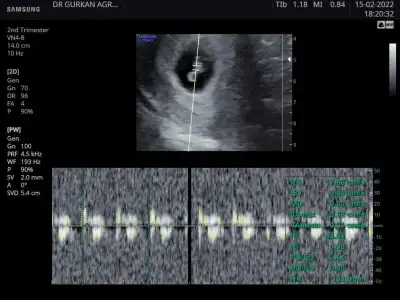

Ben dün akşam gittim bacım kalp atışını duyduk çok şükür rabbim isteyen herkese nasip etsinAynen canım görüntü açısından makina önemliymiş. Doktordan memnun kaldın mı 1 ay sonrasına mi çağırdı artık.

Aynen canım görüntü açısından makina önemliymiş. Doktordan memnun kaldın mı 1 ay sonrasına mi çağırdı artık.

İyice bebek gibi olmaya başladılar maşallahAl canımSana doktor ultrasyon vermedimi fotoğrafını